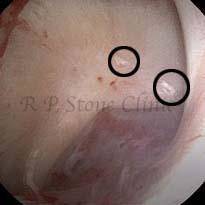

These images are taken as snap shots from the video recording of RIRS Surgery done at our hospital. These are Randall’s Plaques seen with Digital FLEX XC & Digital FLEX XC S. The cream or whitish patches are seen on the tips of RENAL PAPILLAE as seen in images below.

The Below Images Show Small Stones attached to the Renal Papillae.